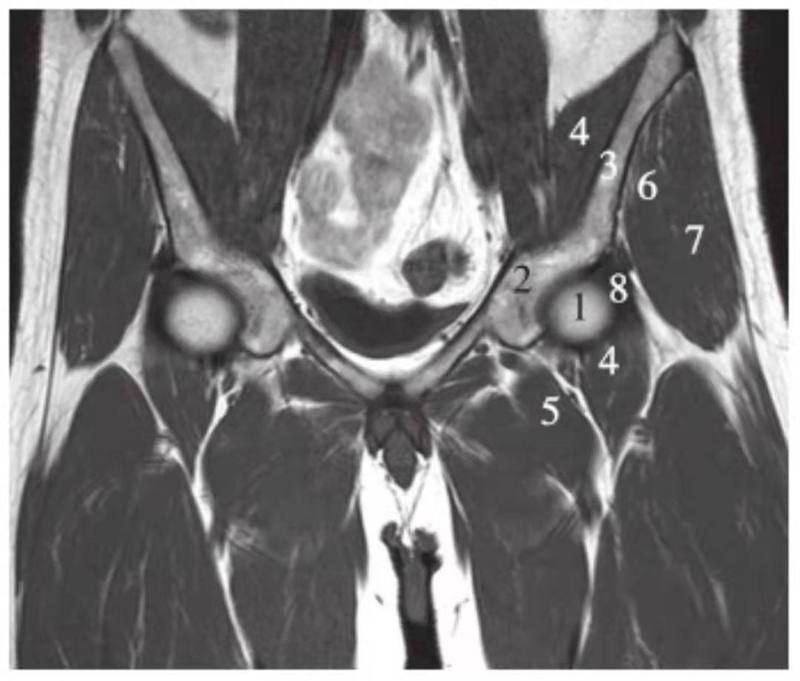

冠状位

正常髋关节经股骨头前缘层面T1WI像

1.股骨头;2.耻骨;3.髂骨;4.髂腰肌;5.内收肌群;6.臀小肌;7.臀中肌;8.关节囊及髂股韧带